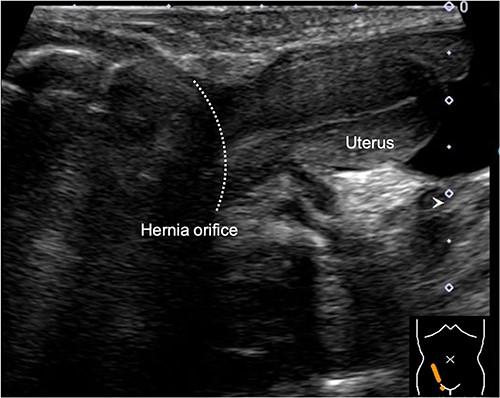

During the newborn’s stay in the NICU, both inguinal regions showed swelling. An ultrasound examination conducted when the infant was 3 months old revealed bilateral inguinal hernias, with the uterus herniating on the right side (Fig. 1). There were no signs of incarcerated hernia, and the urgency of the situation was considered low. As a result, the patient was discharged from the NICU and received outpatient care. At 11 months of age, ultrasound examination was performed, which revealed the presence of omental herniation but no evidence of uterine prolapse (Fig. 2).

Inguinal ultrasound image captured at 11 months of age, showing herniation of the omentum but no apparent protrusion of the uterus.